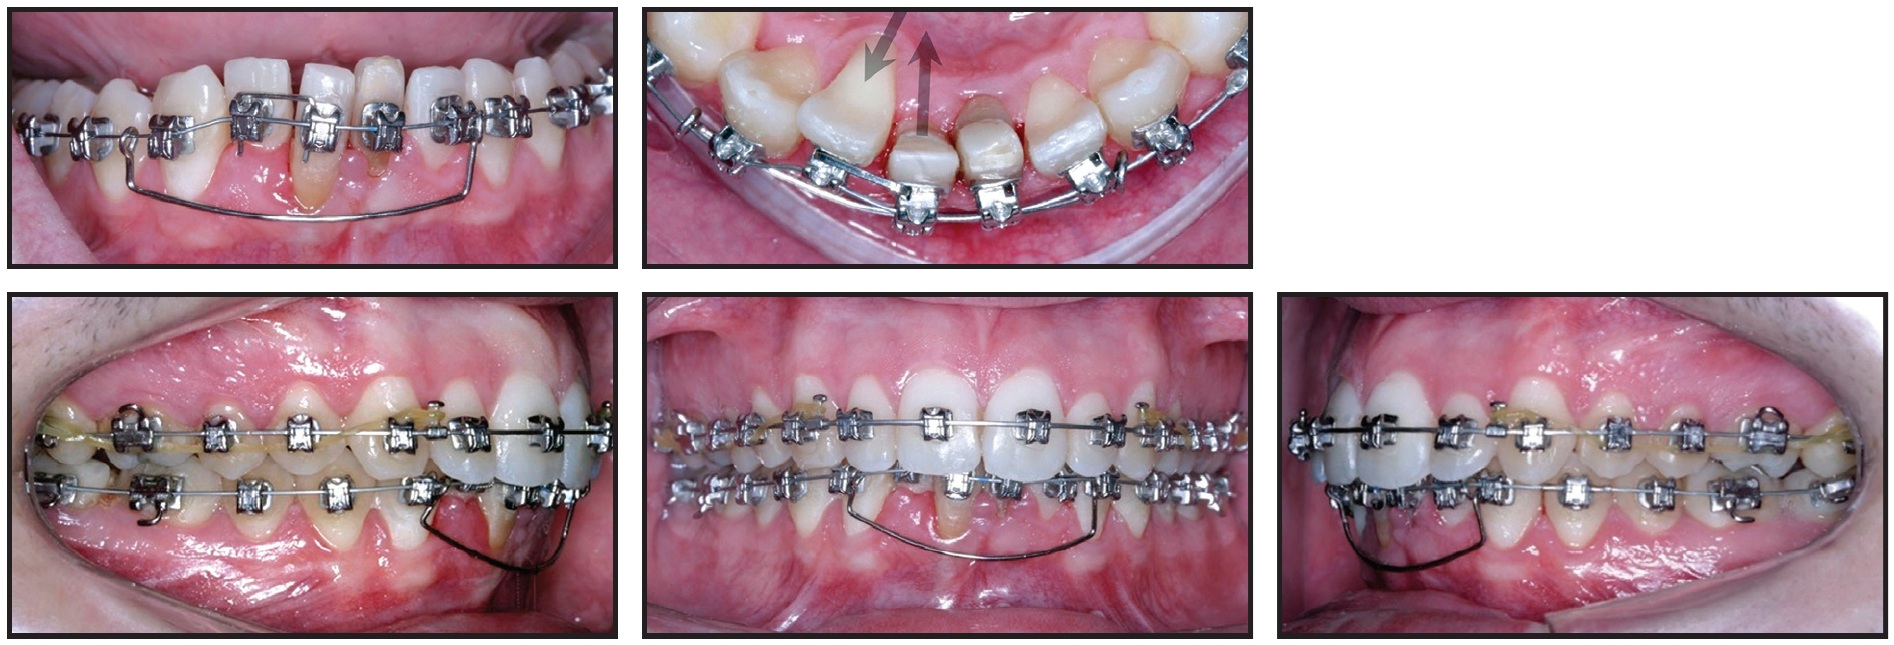

Standard-prescription .022" Damon MX* self-ligating brackets were bonded in both arches, except for the lingually displaced lower right central incisor. One month later, an open-coil spring was inserted mesial to the lower right canine on the initial .014" Copper NiTi archwire to open space for the displaced incisor (Fig. 2).

Fig. 2 Initial .014" Copper NiTi** archwire with U-shaped segmental wire in lower anterior segment.

A segmental U-shaped arch was added and slightly activated distally to control the lower incisors while avoiding any protrusion. The .014" Copper NiTi archwire was maintained for seven months, until the wire was completely passive in the slots, and was then replaced by an .014" × .025" Copper NiTi archwire. Minor interproximal stripping of the lower incisors was performed to facilitate leveling and alignment.

The lingually displaced lower right incisor was bonded after 23 months of treatment, when sufficient space had been opened for its traction and alignment. Torque control was then needed to align the roots of the lateral incisor buccally and the central incisor lingually. Because it is difficult to control torque on a round archwire, an inverted, U-shaped .017" × .017" TMA* segmental wire was inserted into the vertical bracket slots (Fig. 3). The .014" × .025" Copper NiTi archwire was inserted passively to control torque in all teeth until uprighting and alignment were complete.

Fig. 3 After 23 months of treatment, showing torque control of lower right central and lateral incisors with inverted, U-shaped .017" × .017" TMA** wire in vertical slots.

The .014" × .025" Copper NiTi archwire was inserted passively to control torque in all teeth until uprighting and alignment were complete.

In the Damon System, the patient’s archform is recorded with a wax bite registration at this stage, allowing for complete expression of the perioral musculature and the alveolar bone remodeling that occurs after arch expansion.9 The system then provides further expansion in the canine, premolar, and molar regions. In this case, the diagrammed .017" × .025" TMA archwires were inserted after 28 months of treatment for additional torque control and arch preparation. Finishing .019" × .025" TMA archwires were used for the last month (Fig. 4).

Fig. 4 After 34 months of treatment, showing .019" × .025" TMA finishing archwires.